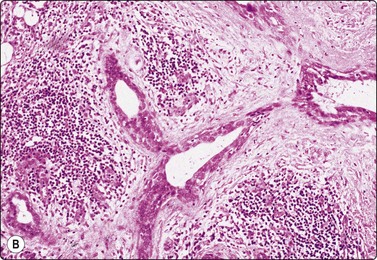

Fig. 4.6 Squamous cell carcinoma

Mainly poorly differentiated malignant cells with large vesicular nuclei and large nucleoli; a few squamous and keratinized cells. FNB smears of cervical lymph node metastasis from squamous carcinoma of larynx (A, MGG; B, Pap, HP).

Squamous cell carcinoma (SCC) is by far the commonest type of carcinoma encountered in the head and neck. Diagnostic criteria are listed in Chapter 8. Lymph node metastases of well-differentiated squamous carcinoma, particularly those arising in the Waldeyer’s ring, have a tendency to undergo liquefactive degeneration (see Fig. 4.3).41 The existence of primary SCC arising in a pre-existing branchial cyst has been doubted and is, in any case, an extremely rare event.42 The distinction from non-neoplastic cysts, mainly branchial cysts has been discussed above. Non-keratinizing squamous cell carcinoma may be represented in smears mainly by small basaloid cells in which case the differential diagnosis includes basal cell carcinoma, pilomatrixoma, poorly differentiated adenoid cystic carcinoma and other small cell tumors. Cells from a poorly differentiated squamous cell carcinoma have large vesicular nuclei and macronucleoli and resemble other anaplastic tumors such as melanoma and large cell lymphoma (Fig. 4.6).